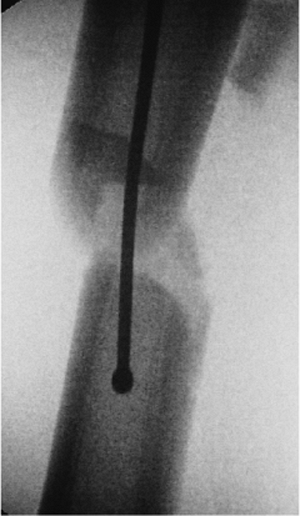

Figure 21.31. A,B.

Proper ball-tip guide-wire placement. A posteriorly placed wire can be seen as central on the AP view. This emphasizes the need to obtain both views to confirm containment of the wire in the medullary canal. |